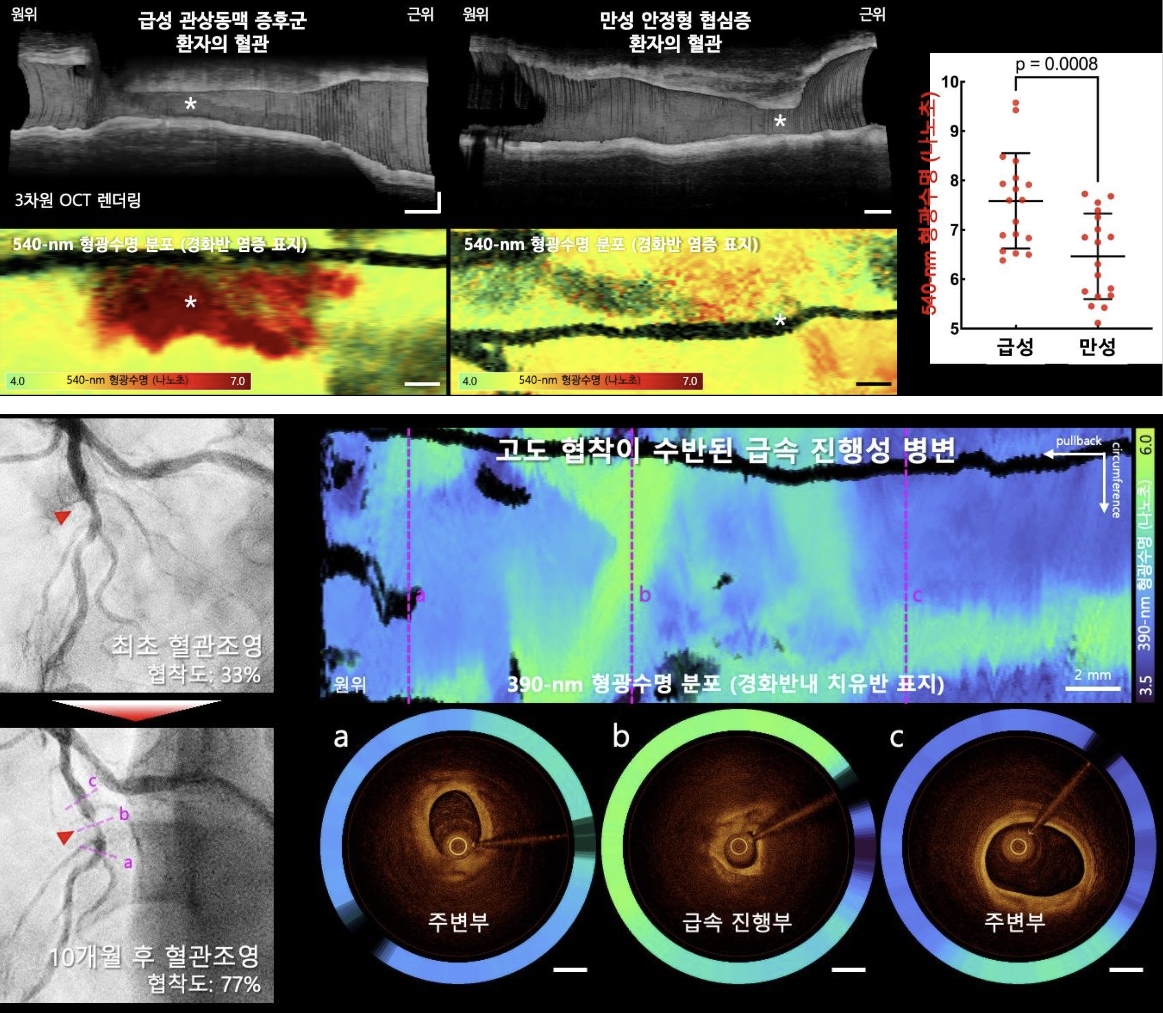

연구에서는 OCT-FLIm 융합영상기술을 활용해 기존 영상기법으로는 평가가 어려웠던 혈관 내 염증, 치유반, 칼슘 침착 등 동맥경화반의 병태생리학적 조성을 정밀하게 영상화하여 정량화했다. 병변 조성이 환자의 임상 상태와 밀접한 연관이 있다는 사실도 입증했다. 급성심근경색과 같은 급성 관상동맥 증후군 환자에서는 만성 안정형 협심증 환자보다 원인 병변의 혈관 염증 지표가 높게 나타났으며, 급속 진행성 병변에서는 반복된 경화반 파열과 치유의 흔적으로 인해 치유반이 광범위하게 분포하는 양상이 확인됐다. 이번 임상시험 과정에서는 모든 참여자에서 영상 획득이 안전하게 완료됐고, 별도의 합병증이나 부작용은 보고되지 않았다.

이번 연구 논문의 제 1저자인 강동오·남형수·김선원 교수는 “본 연구는 관상동맥질환 환자에서 OCT-FLIm 융합영상 기술의 임상 적용 가능성을 세계 최초로 입증한 성과”라며 “FLIm 형광수명 정보를 기반으로 병변 내 염증, 치유반, 칼슘 침착 등을 정량화하고, 질환 활성도와의 연관성을 규명해 개인 맞춤형 치료 및 병변 안정화 평가에 활용할 새로운 진단 플랫폼의 가능성을 제시했다”라고 설명했다.